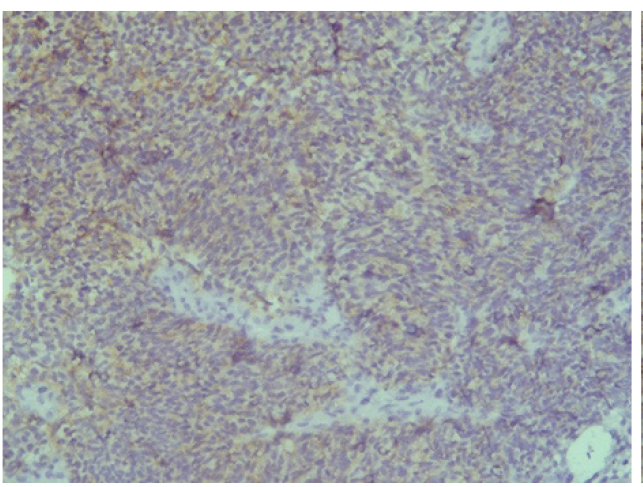

Поэтому при первичном гистологическом исследовании диагноз эстезионейробластомы был установлен только у 6 пациентов (66,6 %), у троих больных (33,4 %) были диагностированы другие формы злокачественного процесса, что не соответствовало клиническим проявлениям. Во всех случаях проводили иммуногистохимическое (ИГХ) исследование. ИГХ-исследование проводили на срезах с парафиновых блоков с использованием антител к Keratin.Pan (AE/AE3), CD45 (Cocktail), Synaptophysin (SP11), ChromograninA (SP12), CD56 (56C04), Ki-67 (30-9), p63 (7JUL)RTU, S100, INI1, CD99 (HO36-1.1). Также выполняли доставку с антителами к EMA (E29), TTF1 (8G7G3/1). В диагностических материалах была отмечена положительная экспрессия Synaptophysin, ChromograninA, CD56, Ki-67 (до 90% ядер), INI1 (рис. 2–6).

Рис. 2. Synaptophysin [SP 11] ×200

Рис. 3. Chromagranin A [SP 12] ×200

Рис. 4. CD 56 [56C04] ×200

Рис. 5. Ki-67 [30-9] (90%) ×200

Рис. 6. INI 1 ×200

Эти результаты иммуногистохимического исследования подтверждают наибольшее соответствие иммунофенотипа опухоли – ольфакторной нейробластоме (G3 по Hyams) М9522/33.